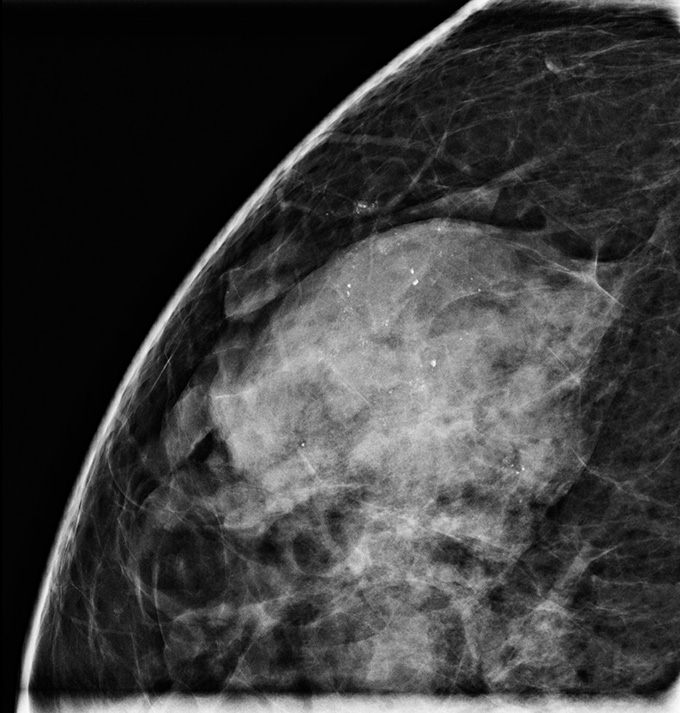

Mammographie d'un sein présentant un carcinome à tissus denses et canalaire in situ, également appelé cancer du sein de stade 0. Le CCIS apparaît sous la forme de petites taches blanches.

Une nouvelle étude portant sur 957 femmes a évalué s'il était sécuritaire d'effectuer une surveillance active d'une forme à faible risque de carcinome canalaire in situ, ou CCIS – un cancer non invasif, souvent appelé cancer du sein de stade 0, qui ne s'est pas propagé au-delà des canaux galactophores. — comme alternative à la chirurgie (SN : 30/08/24).